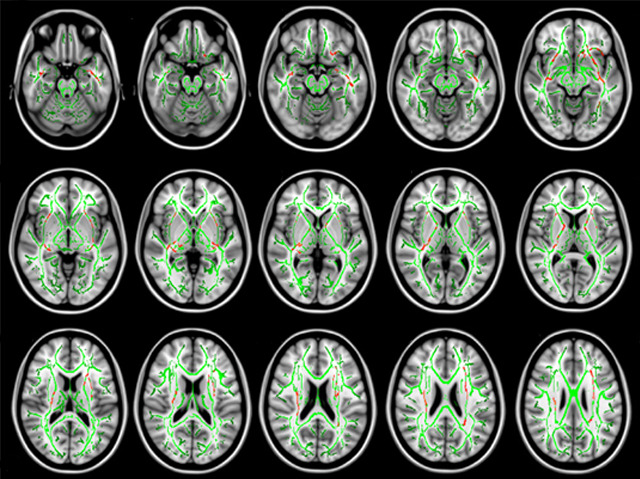

There’s fretting and then there’s generalised anxiety disorder (GAD), a condition characterised by chronic and excessive worry about everyday things. Brain-imaging studies have suggested GAD is associated with abnormal neural circuitry in brain regions involved in emotional regulation. Most studies have focused on neuron-loaded grey matter but researchers are turning to white matter, which is composed of nerve fibres and fires signals between disparate regions of grey matter. Looking closely at teenage brains, researchers have now found that this white matter network is degraded in adolescent GAD patients. Pictured is an image, cut in to lateral cross-sections, of an approximation of the average white matter network (green) in 25 teenagers with GAD and 24 healthy controls. The red parts mark sections where it has been significantly reduced in GAD patients compared to healthy teenagers. It appears that this degradation, by disrupting within-brain communication, may play a key role in inducing chronic anxiety.